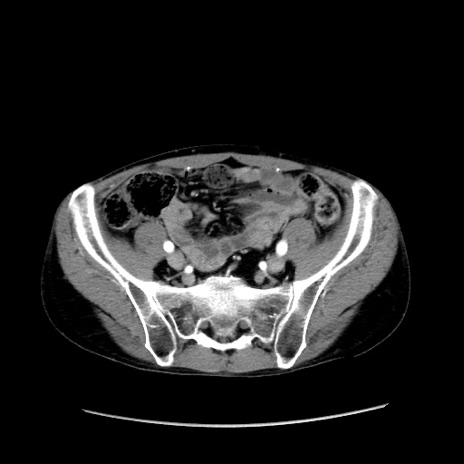

症例37(横断像)

【症例】40歳代 男性

【主訴】腹痛

【現病歴】4時間ほど前に電車に乗車中に臍部上より腹痛出現。徐々に増悪し起立困難となり、救急外来受診。生ものは数日食べていない。今朝お雑煮を食べた。

【身体所見】BT 36.8℃、BP 117/84mmHg、HR 91/min、SpO2 97%、苦悶様、腹部:臍上部広範囲圧痛あり、反跳痛±

【データ】WBC 8100、CRP 0.03